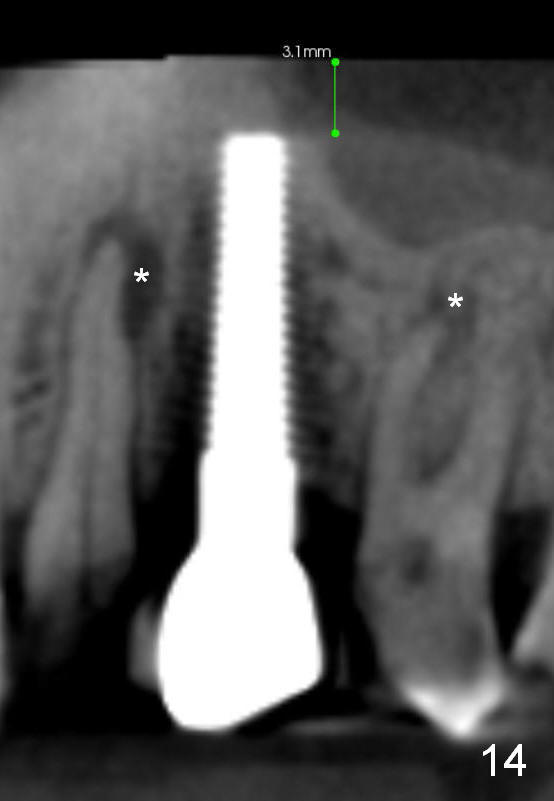

Eight months post cementation, CBCT shows periapical infection of the neighboring teeth (Fig.14 *). There is still apical bone for a longer implant (Fig.14 green line, Fig.15 *). The implant functions 1.5 years post cementation. When the implant at the lower bicuspid fails, the patient reveals that he is a diabetic. The latter is the main reason of delayed healing.